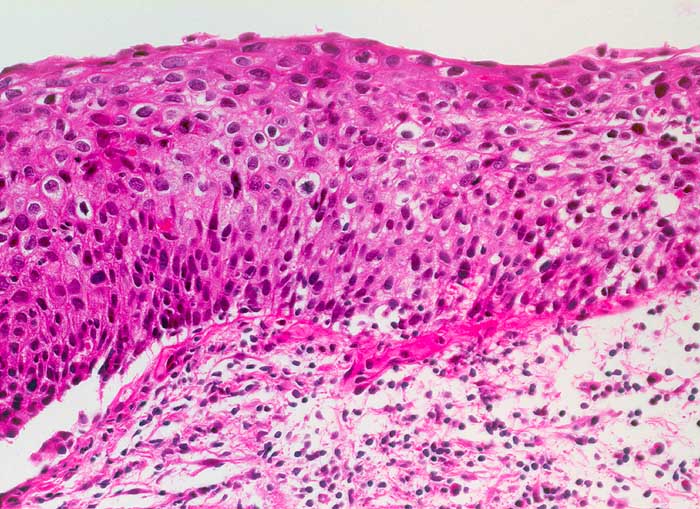

PathoPic – image database / PathoPic ID 6586 - schwere Dysplasie des Plattenepithels CIN 3

schwere Dysplasie des Plattenepithels CIN 3

Deutliche Kernvergrösserung und Kernatypien sowie Polaritätsverlust der Epithelzellen in der gesamten Epithelbreite. Lediglich die Kerne der obersten Epithelschicht zeigen eine Ausreifung und sind abgeflacht. Suprabasale Mitose.